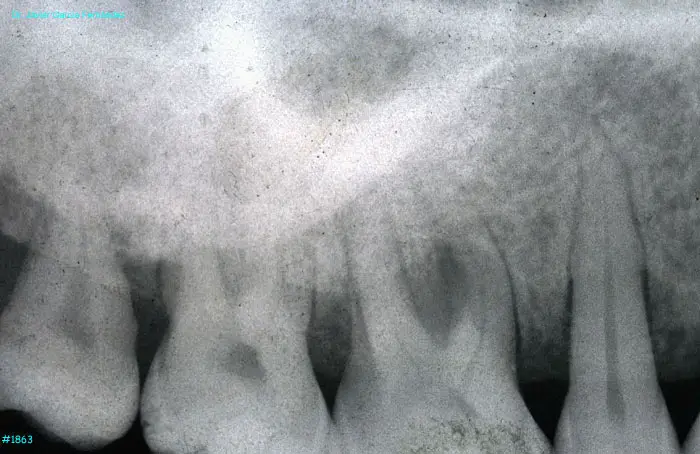

image 14